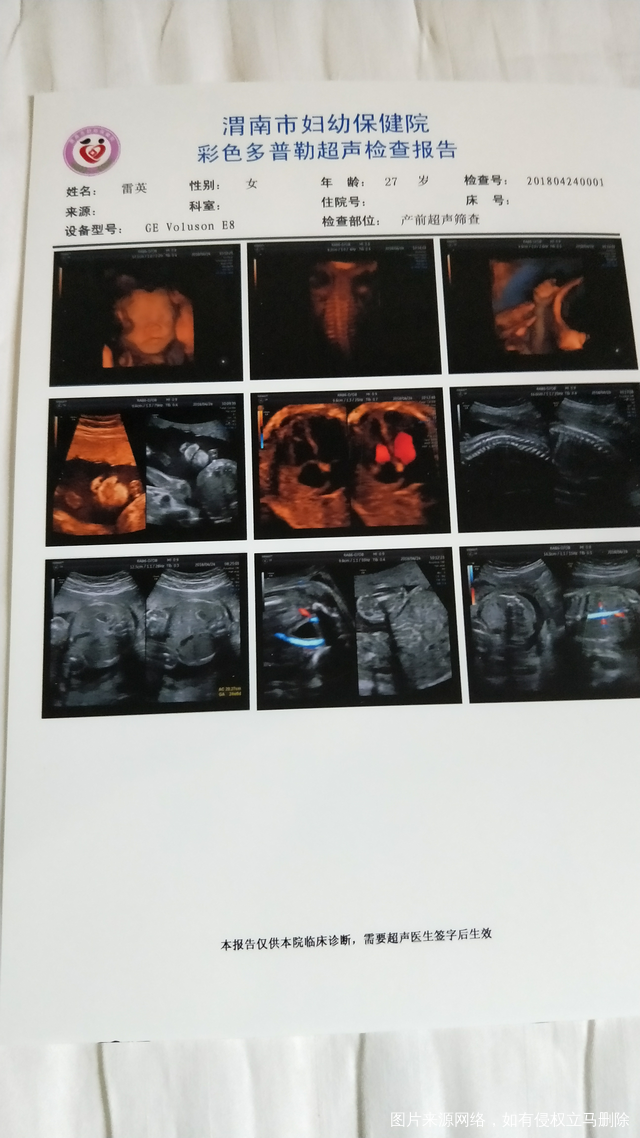

试管婴儿怀孕24周加1天

更多医生麻烦帮忙看看报告是否正常有地中海贫血吗